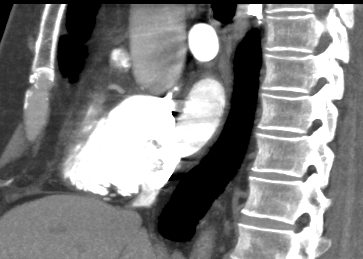

Компьютерная томография сердца является высокотехнологичным лучевым методом исследования, который позволяет оценить строение и особенности анатомии камер сердца, визуализировать состояние перикарда, коронарных артерий и восходящей части и дуги аорты.

В нашей клинике КТ сердца проводится на новейшем 128-срезовом мультиспиральном компьютерном томографе экспертного уровня TOSHIBA AQUILION CXL. Томограф послойно сканирует анатомическую область сердца, производя срезы толщиной от 0,5 мм. Методика сканирования сердца 128-срезовым КТ сканером производится с использованием перспективной синхронизации по электрокардиографии (ЭКГ).

Протокол сканирования предусматривает внутривенное болюсное контрастирование. Контрастное вещество на основе йода вводится пациенту внутривенно непосредственно во время исследования. Контраст равномерно распределяется по сосудистой системе, благодаря чему становится хорошо видна восходящая часть аорты с отходящими от нее венечными артериями и дуга аорты. По результатам обследования можно решить, нуждается пациент в проведении стентирования коронарных артерий или нет.